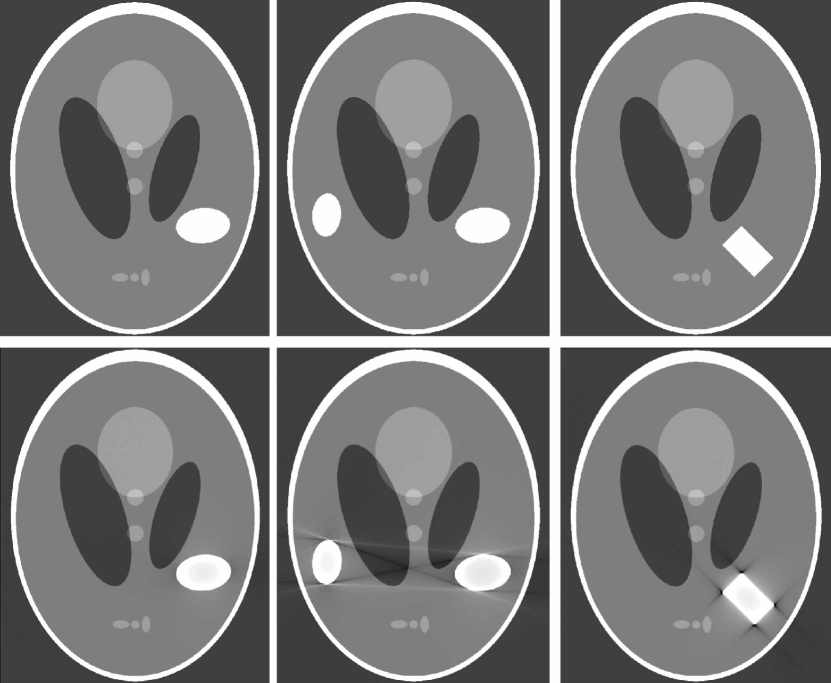

| (36) |

only when if the metal region is not strictly convex. In other words, the streaking artifacts in are related with the geometry of , as shown in Fig. 4. In the figure, we use the Shepp-Logan phantom as and the homogeneous metallic objects with the various geometries are added to illustrate the streaking artifacts in the reconstructed image .

According to Theorem 3.1 and Proposition 1, metal streaking artifacts are due to the severe nonlinearity of the X-ray data with respect to the geometry of the metallic subject . Metal streaking artifacts are included in the union of tangent space , which is a tangent space of another point . In the case of single metallic object with a strictly convex boundary, the reconstructed CT image has no streaking artifact. If consists of two simply connected domains and with boundaries respectively, there are four different tangent lines touching both the metal domains and .

The following corollary explains that the nature of the scatter artifacts is similar to the beam hardening artifacts and Fig. 5 (b) shows these phenomena described in DeMan1998 ; Glover1982 .

Corollary 1 implies that the streaking artifacts due to Compton scattering can occur between bones and metals, even when (See Fig. 5 (b).)

One of other potential sources of metal artifacts is photon starvation, which occurs when insufficient (possibly zero) photons reach the detector as the X-ray beam passes through a metallic object. This photon starvation generates a similar effect to the noise effect in the metal region Barrett2004 , and the noise contribution is greater from projections that pass through metallic objects than from those that do not. Consequently, these noise effects lead to serious streaking artifacts in the reconstructed image at the points where the beam passes through metallic objects. Numerical and experimental results of streaking artifacts due to photon starvation are well depicted in works by Barrett2004 ; Mori2013 ; vZabic2013 . Streaking artifacts due to photon starvation are verified to be prominent along lines passing through multiple or strong objects with high attenuation coefficients (e.g. metal). Finally, we should mention that streaking artifacts caused by scattering, noise, and photon starvation can be amplified when they are associated with metallic objects Barrett2004 ; DeMan1998 ; Mori2013 ; vZabic2013 (See Fig. 6).

To validate our main results in the clinical CT case, we include CT image of one author’s teeth and mandible in Fig. 6. As shown in this figure, most streaking artifacts occur along the tangent line of boundary of metallic objects. Besides, due to scattering and/or noise effect, the streaking artifacts can occur between the metallic object and the bone, as described in the corollaries of this section.